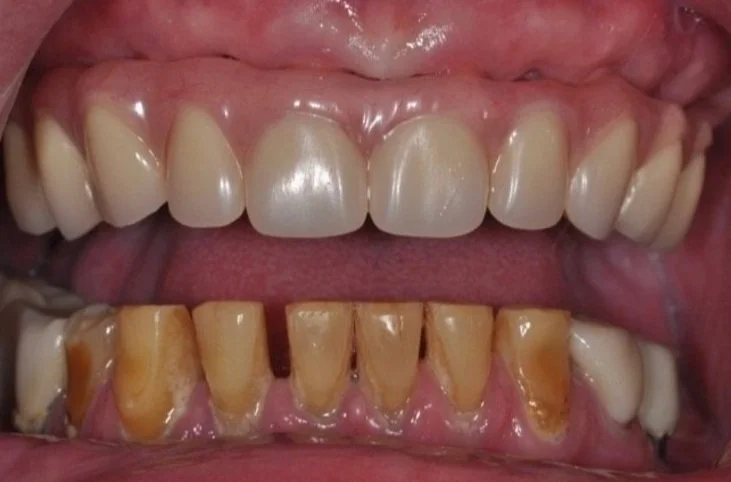

How We Restored a Front Tooth with a Dental Implant — Start to Finish

When it comes to your smile, the front teeth do all the talking.

They’re what people notice first. So when a front tooth is missing or damaged — whether from trauma, decay, or failed restorations — it’s not just about replacing it. It’s about doing it perfectly in the smile.

In this case study, we’ll walk you through one of the more complicated — and rewarding — procedures we do at our practice: a front tooth dental implant. You’ll see how much thought, planning, and precision goes into restoring one small tooth… and why every step in the dental implant process matters.

Unlike molars, where strength matters to a higher degree, replacing a front tooth is has much to do with aesthetics, symmetry, and subtlety, in addition to bite force management.

Here’s why it’s such a technical and artistic challenge:

Any tiny mismatch is obvious. The color, shape, gumline — everything has to match the neighboring teeth.

The bone and gum are thin. That makes it easier for collapse or shadowing to occur.

We’re working in the “esthetic zone.” This area demands precise planning, sculpting, and soft tissue support. Thankfully all our doctors have advanced training in cosmetic dentistry.

Over the next few weeks or months, we monitor soft tissue healing. Sometimes we adjust the temporary to guide gum shaping. Patience here pays off — rushing this stage can lead to esthetic failure. One of the biggest risks in front teeth implants is gum recession!Final Crown

Once everything is stable, we place the final custom crown. Shade, translucency, shape, and surface texture are all matched to your natural teeth so the implant blends in seamlessly.

“How natural will it look?”

If all the steps are followed carefully — especially tissue shaping and crown customization — it will be nearly impossible to tell it’s not your original tooth. Check out our video case study to see more.

Replacing a front tooth with an implant isn’t just dental work — it’s dental artistry. Cosmetic dentistry is more than just placing an implant in your jawbone. And when it’s done right, the result is a smile that looks and feels completely natural.